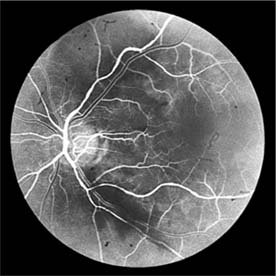

In contrast, elderly patients with arteriosclerotic vessels are unable to respond in this manner, and their vessels are thus protected by the arteriosclerosis. It is for this reason that elderly patients seldom exhibit florid hypertensive retinopathy (Figure 15-11).

Figure 15-11

Figure 15-11: Accelerated hypertension. Fluorescein angiogram in an elderly wom.an showing marked arteriolar constriction and irregularity but few signs of florid retinopathy.

Fluorescein angiography has made possible accurate documentation of these microcirculatory changes. In young patients with hypertension, arteriolar attenuation and occlusion are seen, and capillary nonperfusion can be verified in relation to a cotton-wool spot, which is surrounded by abnormal dilated capillaries and microaneurysms with increased permeability on fluorescein angiography.

Resolution of the cotton-wool spots and the arteriolar changes occurs with successful hypotensive therapy. In elderly patients, the underlying arteriosclerotic changes are irreversible.